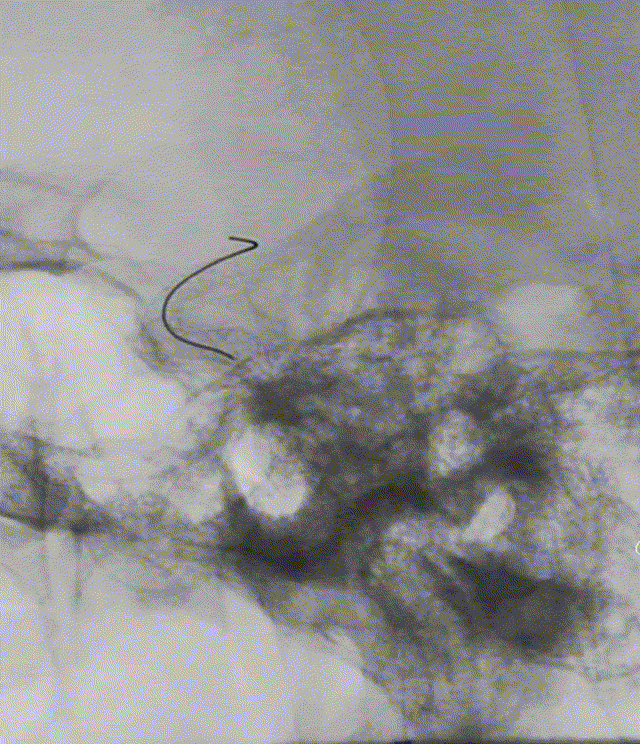

4. 编织网丝/方式决定支架较硬,带来径向力强的优势;CAT5跟进按摩甚至是长鞘也很少导致支架卷曲套叠

5.支架通体显影,但有时需要多角度观察、稀释造影评估贴壁情况;